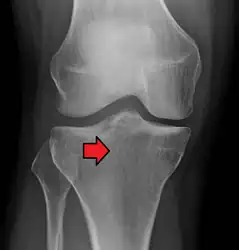

Subtle tibial plateau fracture on an AP X ray of the knee -

Lipohemarthrosis due to a tibial plateau fracture -